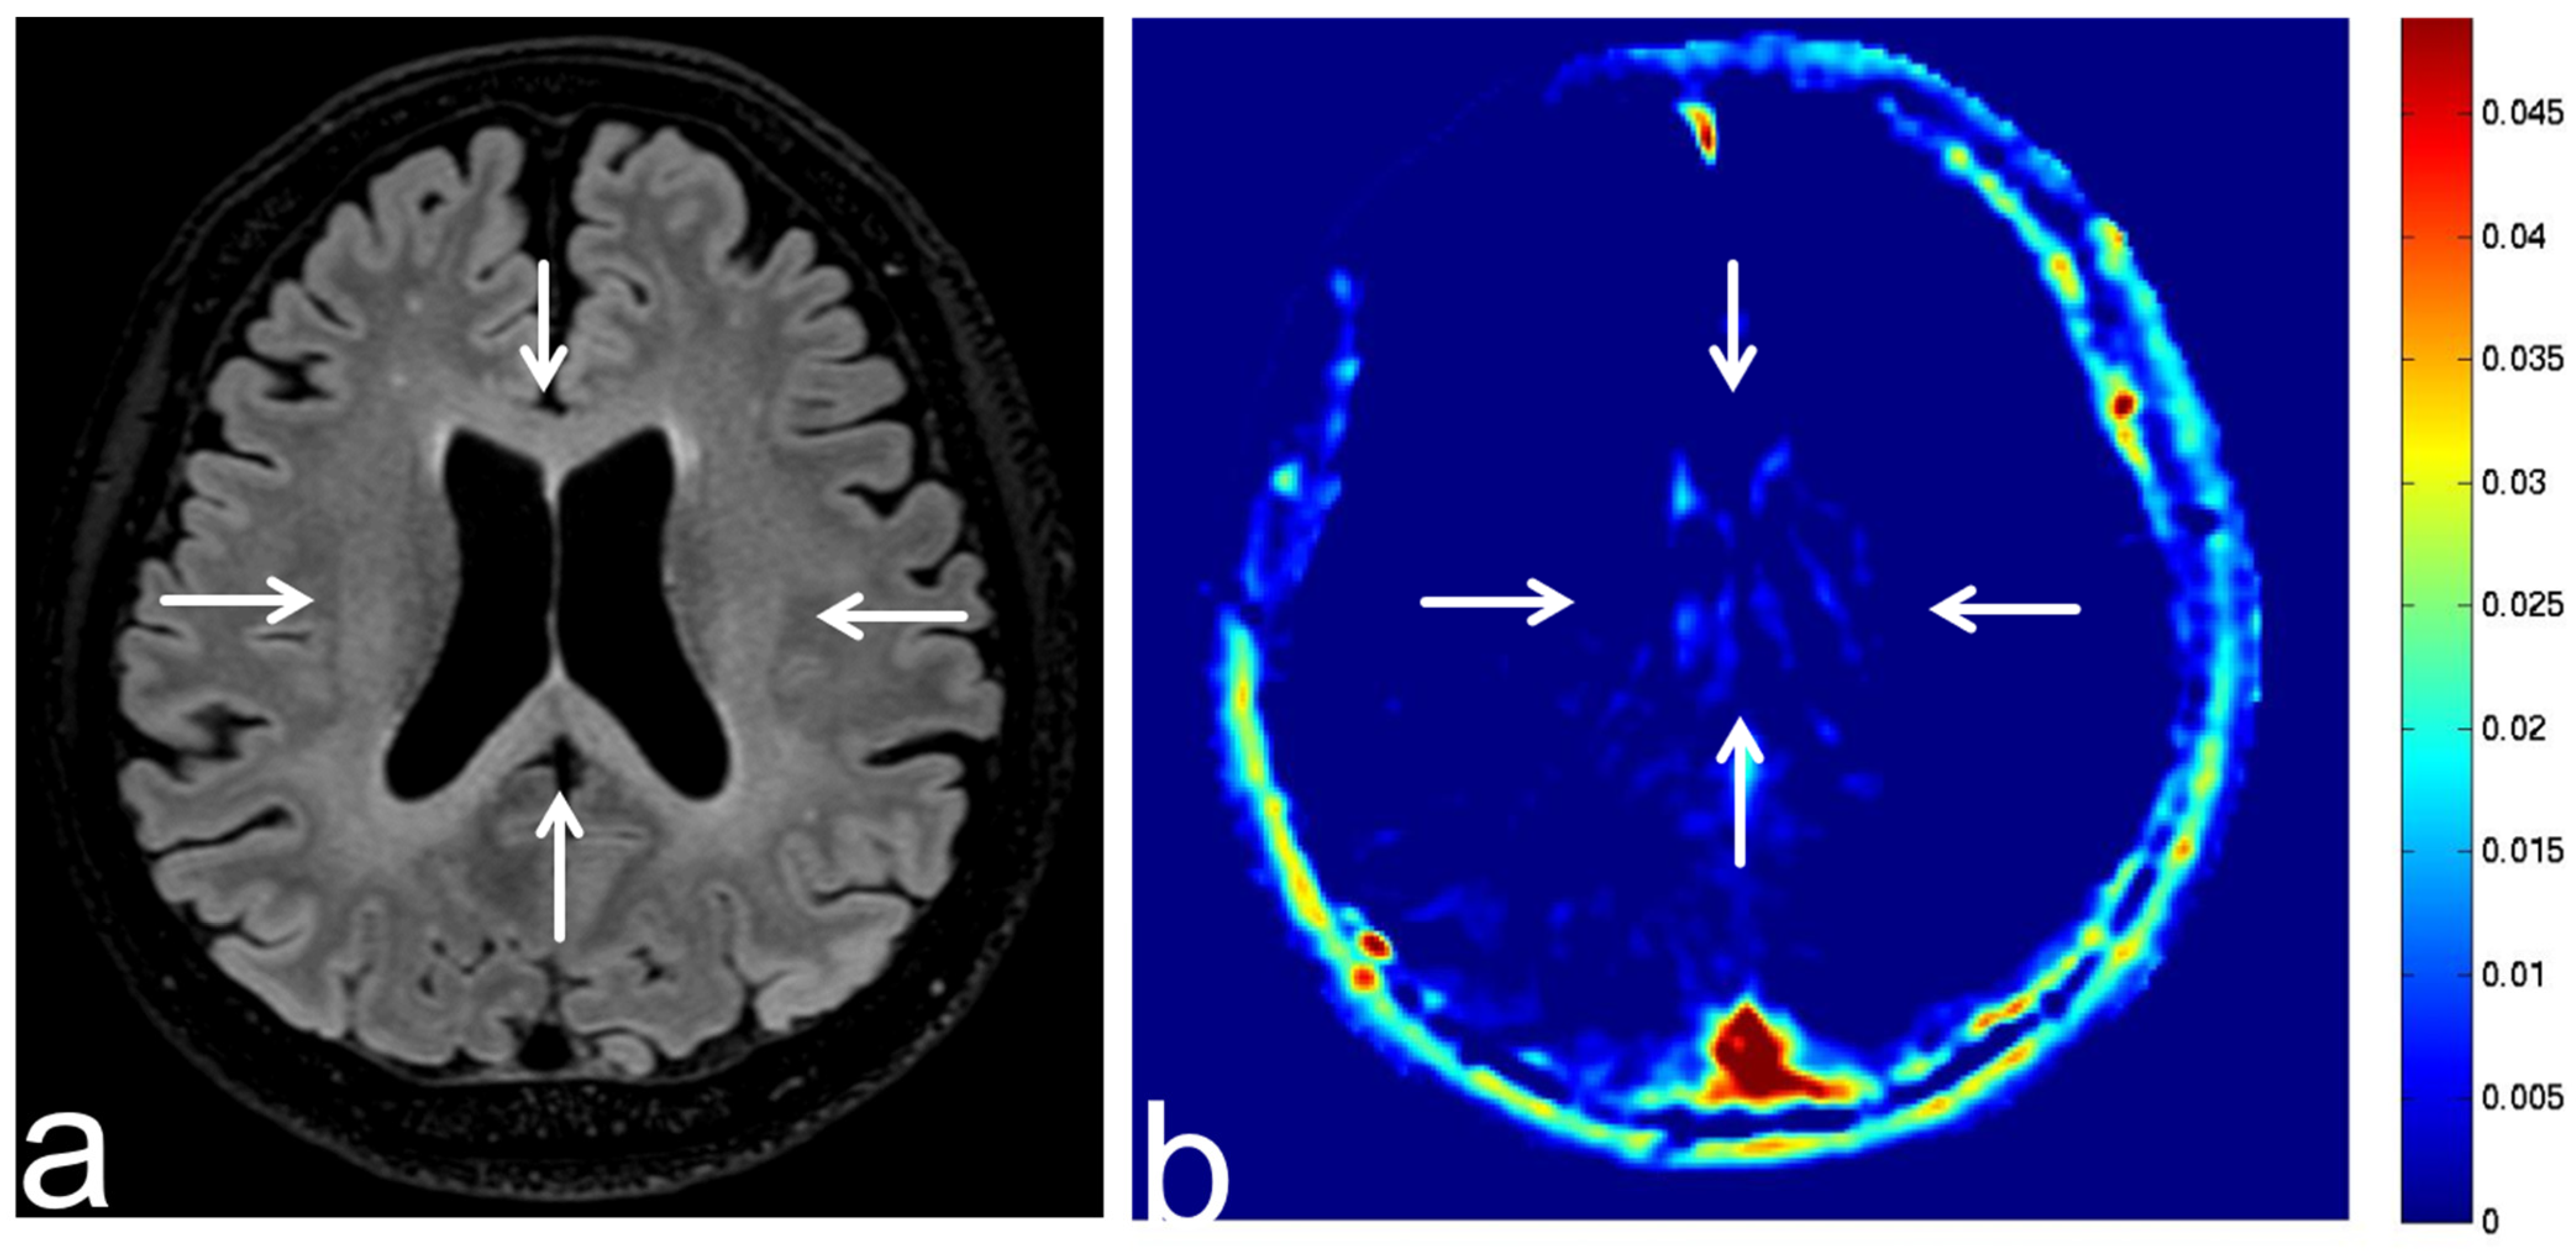

8.1. Radiation Necrosis

8.2. Leukoencephalopathy

8.3. Tuberous Sclerosis Complex

8.4. Progressive Multifocal Leukoencephalopathy